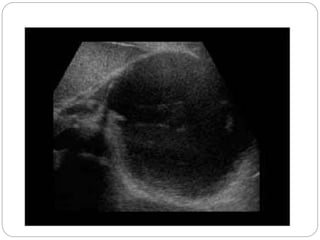

Adjacent

to spleen

with

evidence

of

layering

debris